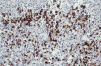

FIG. 4.-- Las células linfoides grandes muestran positividad para el CD30.

El estudio histopatológico de una de las lesiones cutáneas (Fig. 2) evidenciaba una epidermis hiperplásica, con discreta espongiosis e hiperqueratosis paraqueratósica, con abundantes polimorfonucleares en la capa córnea; bajo ella se observaba un denso infiltrado celular superficial y profundo constituido por linfocitos, células atípicas de aspecto linfoide con núcleos grandes y cromatina en grumos y gran cantidad de eosinófilos (Fig. 3). El estudio inmunohistoquímico demostraba una proliferación linfoide de inmunofenotipo T (CD3, CD43 positivo), con positividad para CD30 (Fig. 4), con índice de proliferación (Ki67) del 20%, estableciéndose el diagnóstico histopatológico de infiltración por linfoma T CD30 positivo, compatible con PL tipo A.